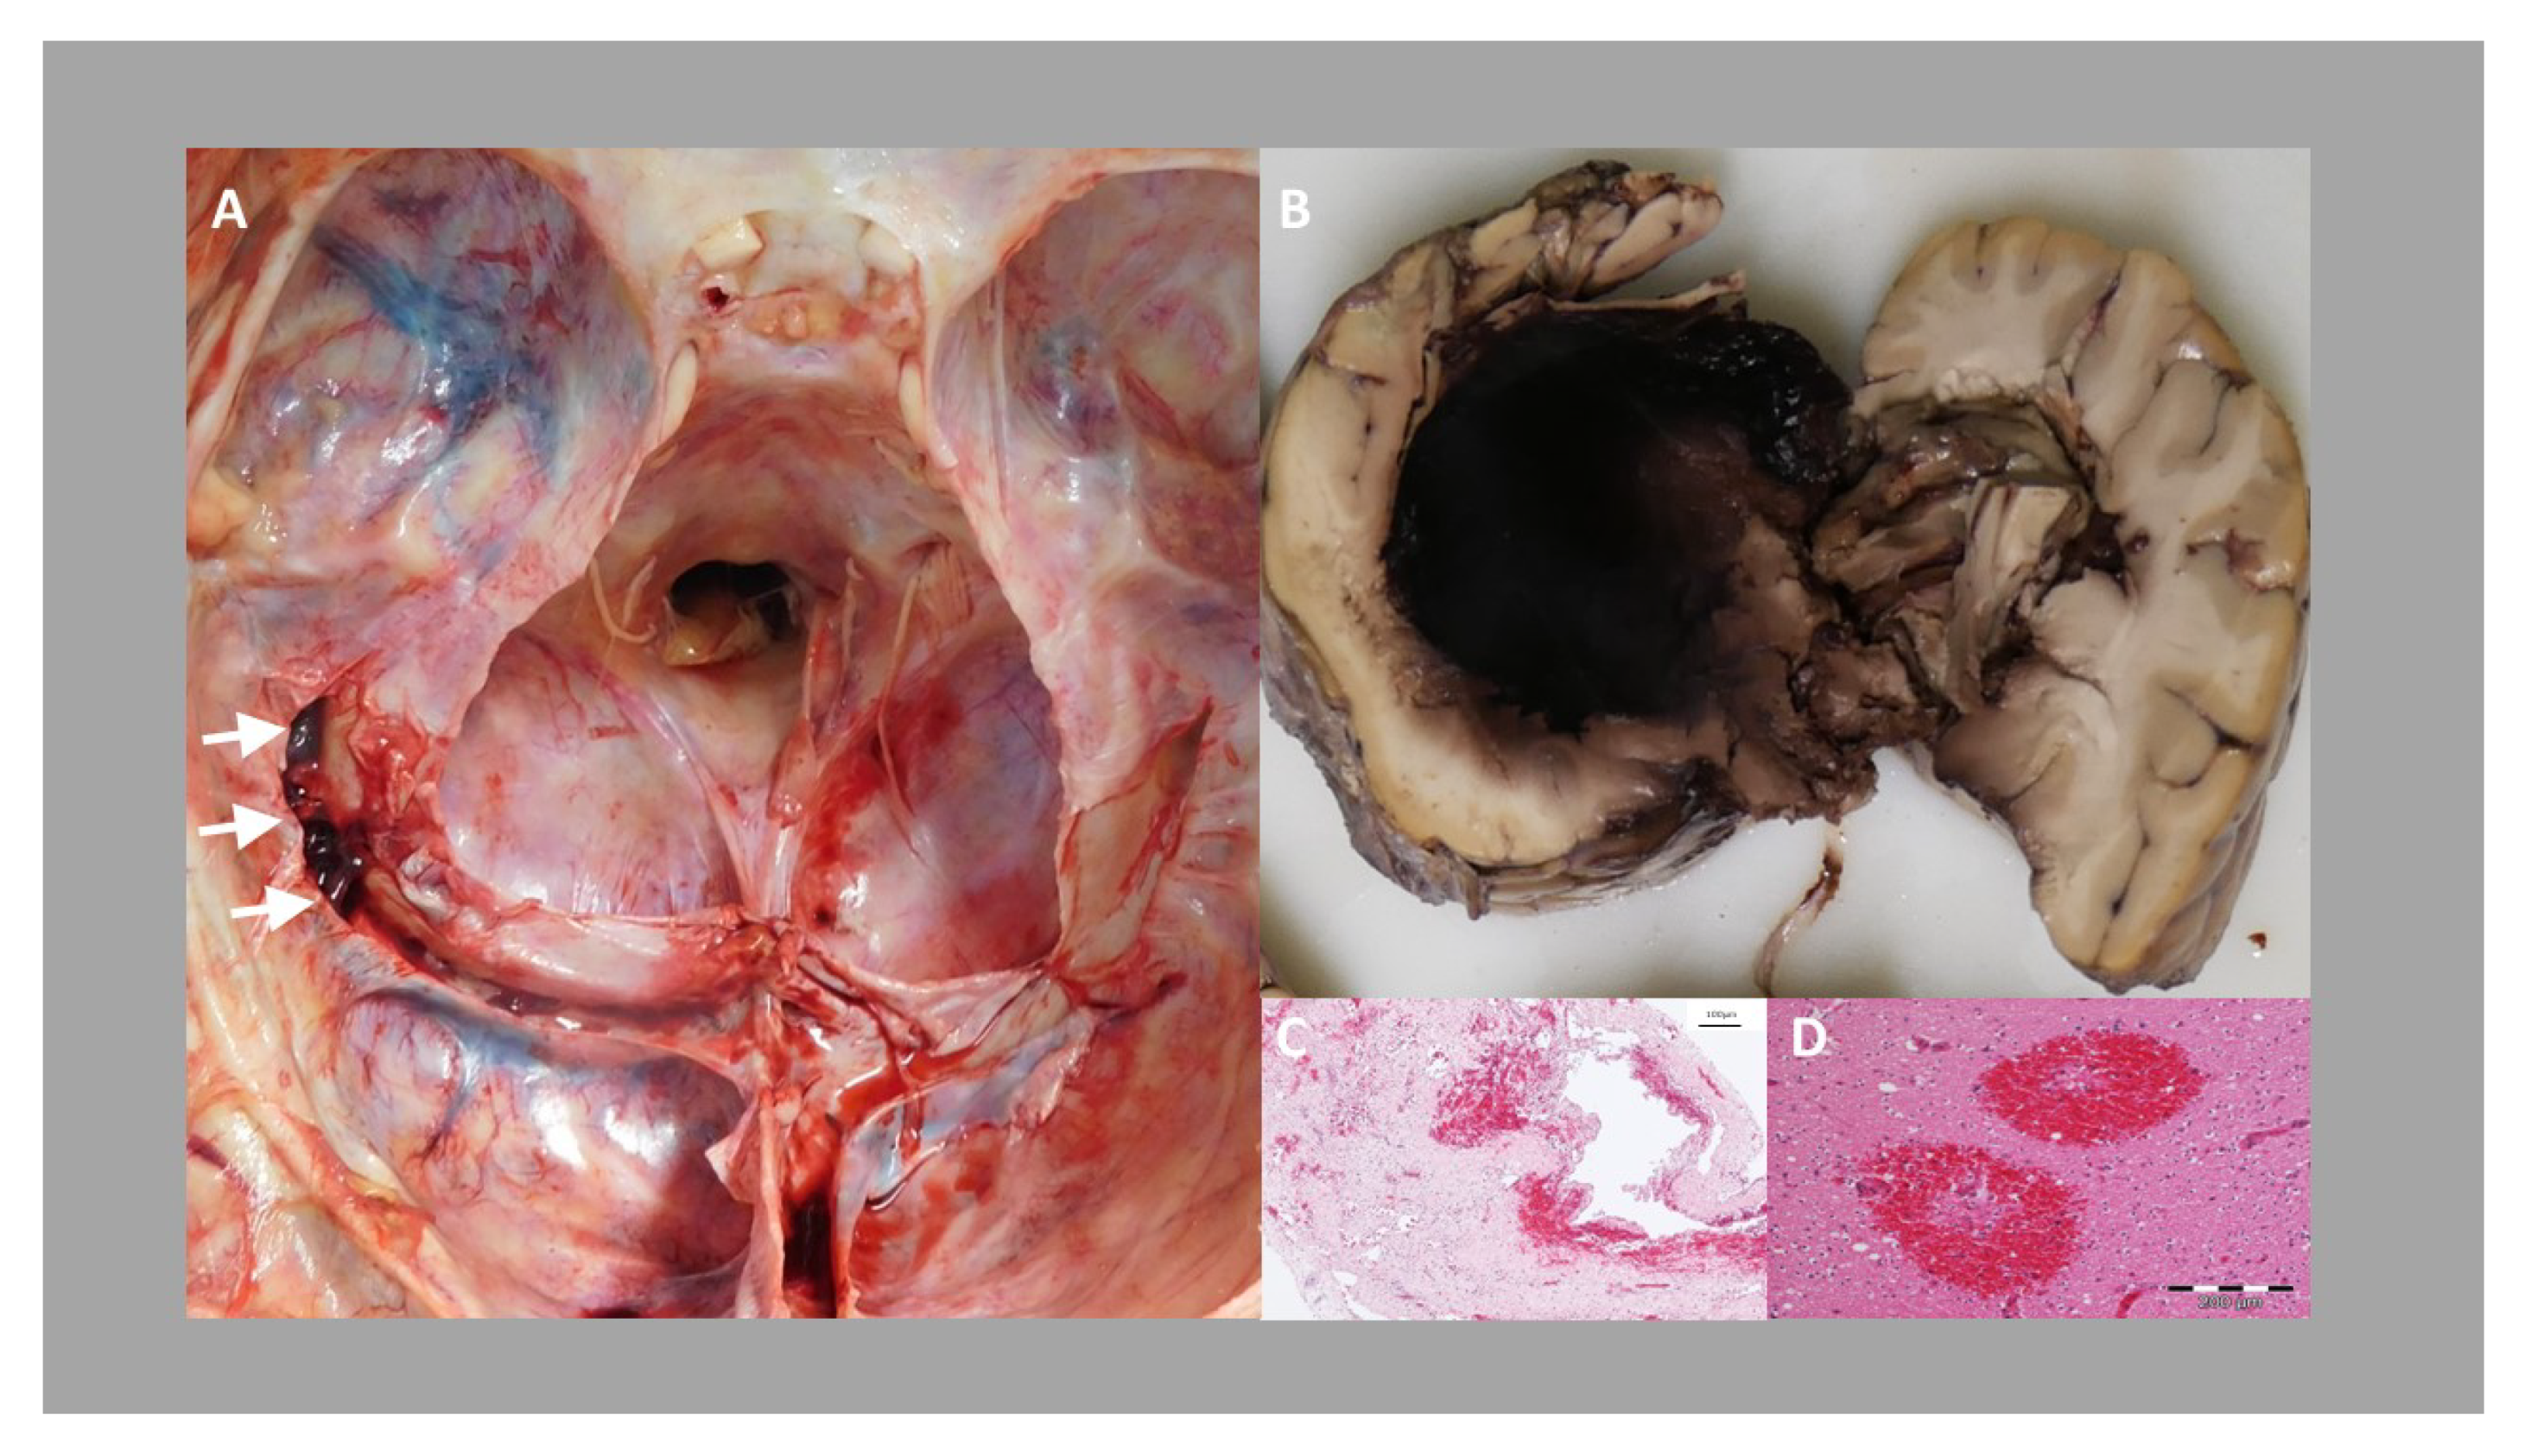

4. Laboratory Investigations

5. Forensic Obduction

6. Discussion